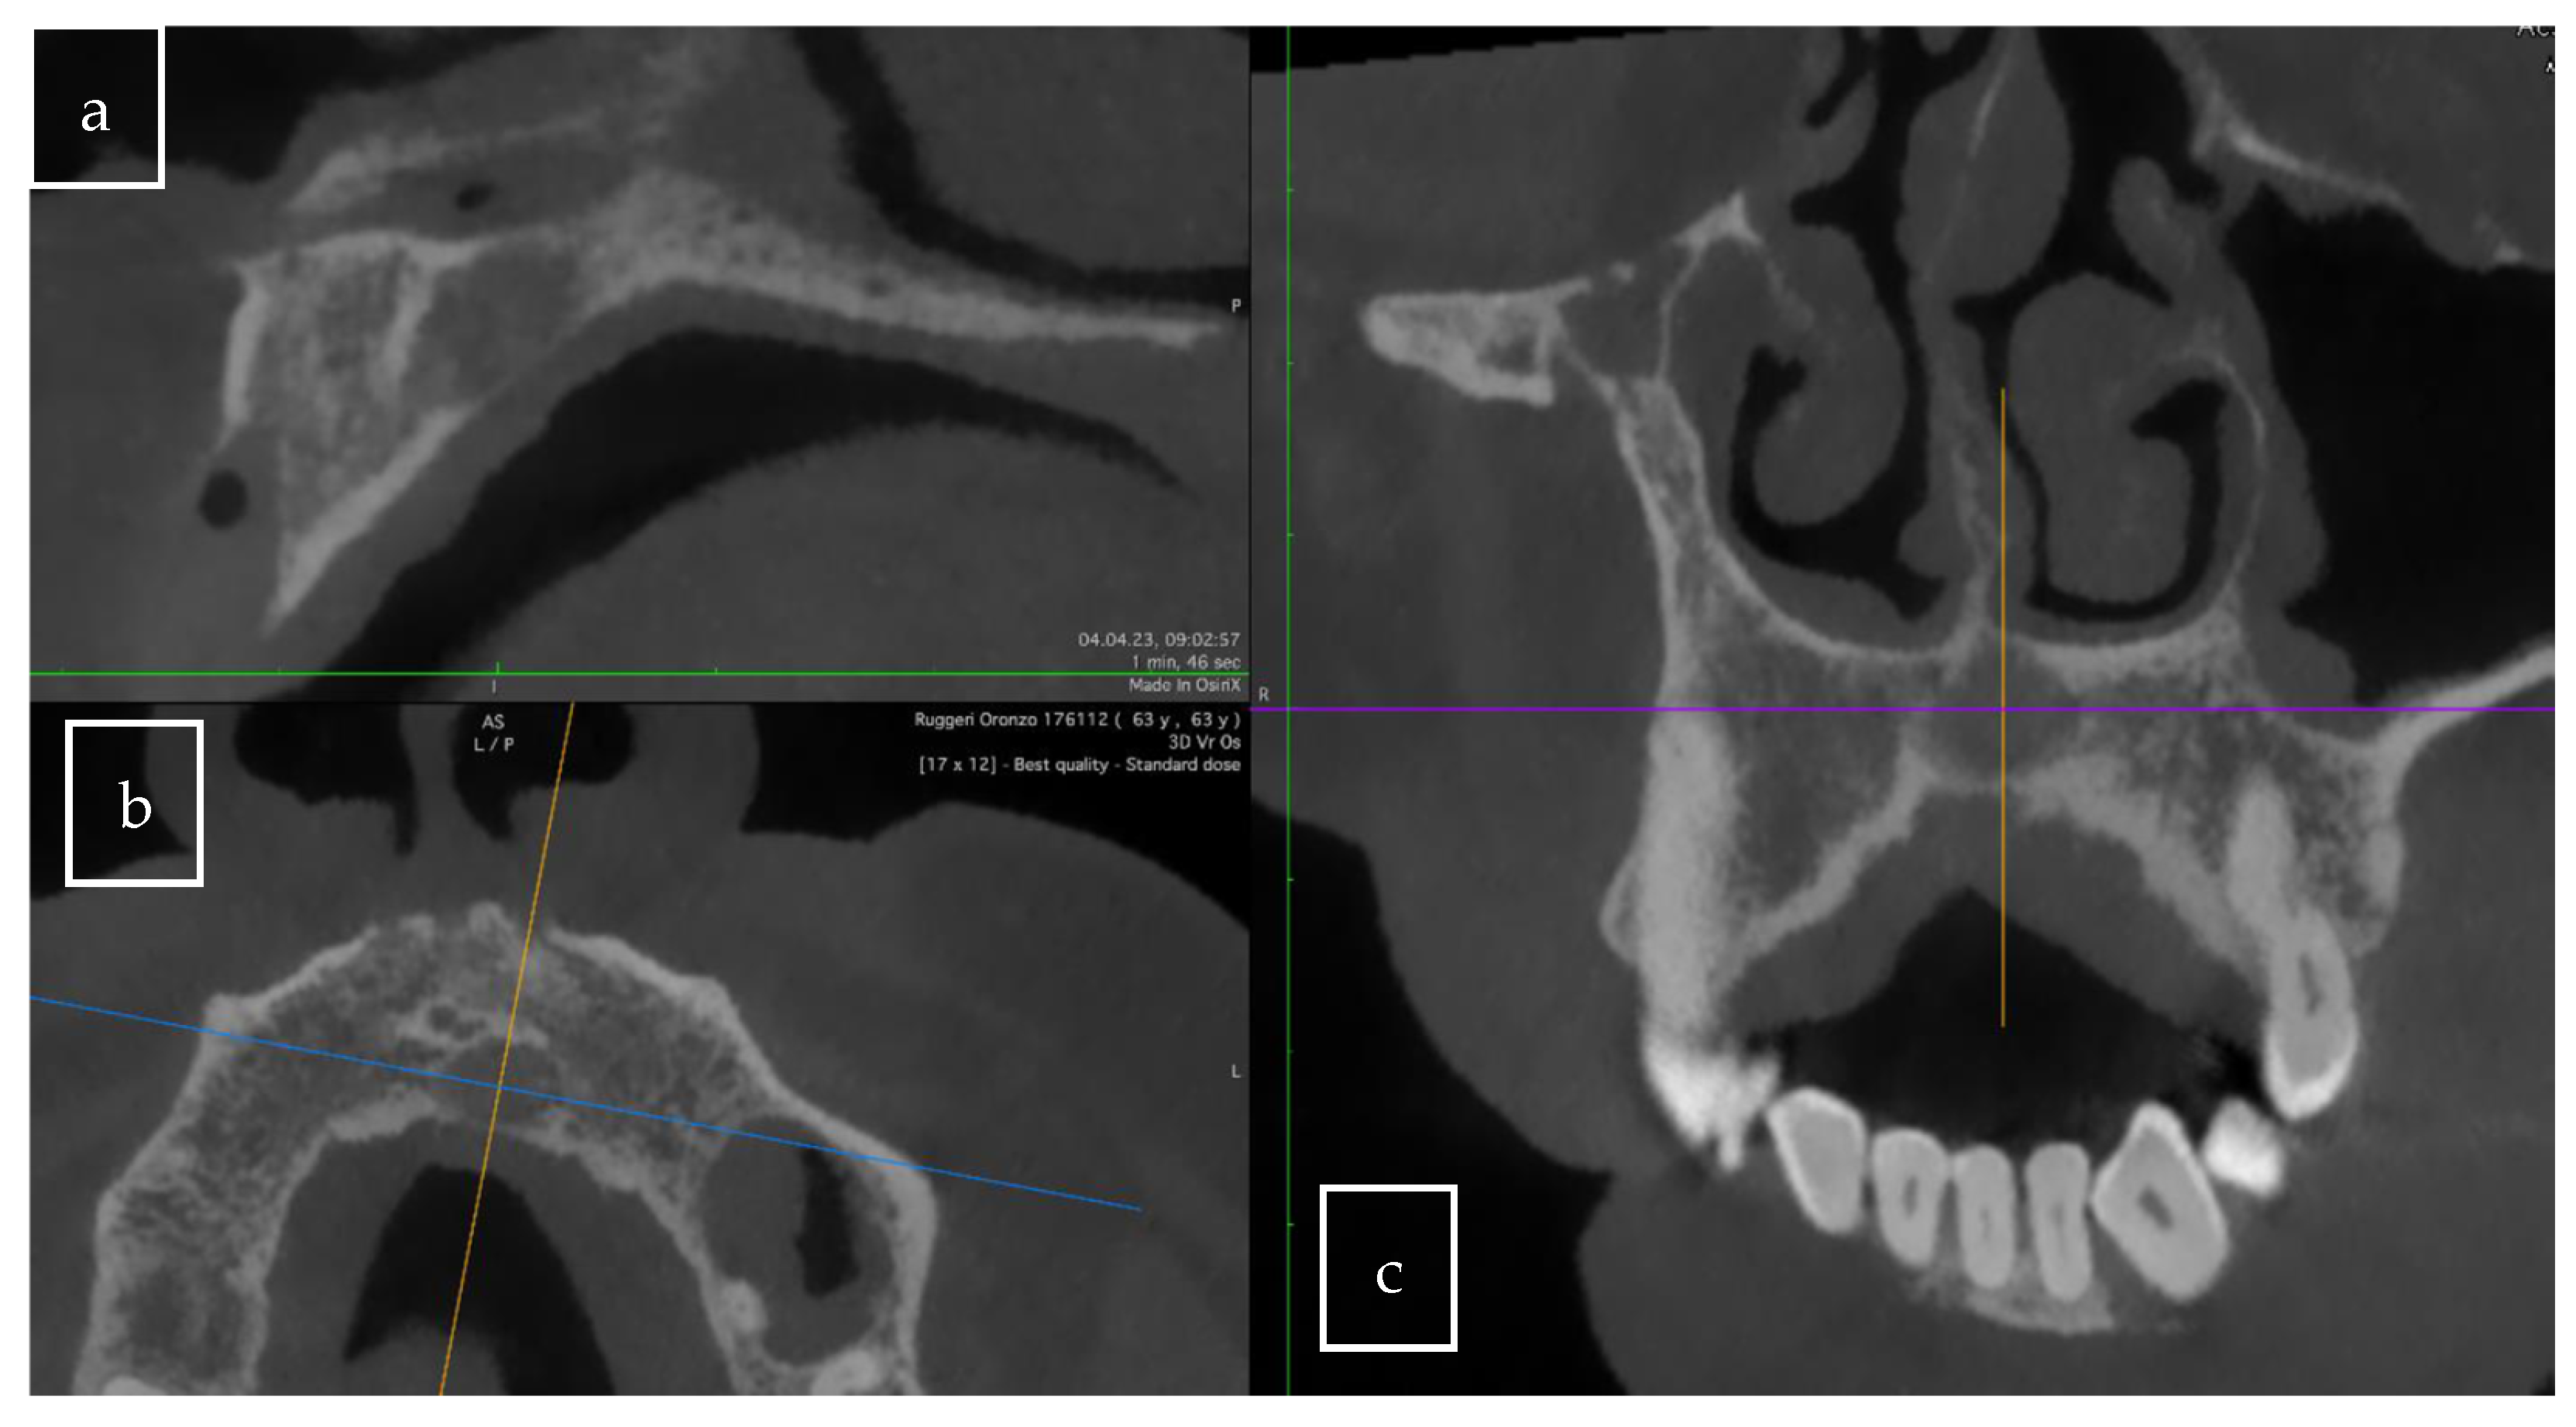

3.2. Case Presentation

| Our case | Case report | 1 | M | 63 | Asymptomatic | Right palate | Surgical excision | 9 × 8 × 12.5 mm | Radiolucent |